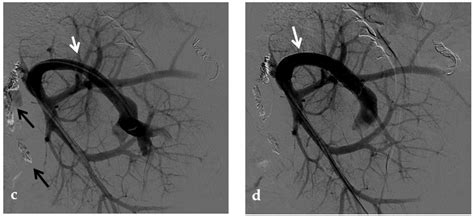

Confirming a diagnosis of Portal Vein Thrombosis requires advanced imaging techniques to visualize the blood flow and the clot itself. Physicians will typically utilize non-invasive tools as the first line of defense.

CT Angiography Provides detailed, cross-sectional images of the abdomen, clearly highlighting the thrombus and the extent of the blockage.

• Interventional Radiology: In severe, treatment-resistant cases, procedures such as Transjugular Intrahepatic Portosystemic Shunt (TIPS) may be necessary to bypass the obstructed vein and relieve portal hypertension.